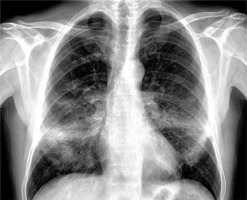

A 56-year-old man with stage IV non-small cell lung cancer (NSCLC) presented to the emergency department with progressive dyspnea and hypoxia. He had been diagnosed with adenocarcinoma of the right upper lobe 16 months earlier. PD-L1 expression in the tumor was 2%, and no other gene driver mutations were detected. The patient initially received treatment with a combination of platinum-based chemotherapy and immunotherapy (pembrolizumab). After the initial partial response to treatment, the patient remained in consolidation therapy treated only with pembrolizumab (Keytruda) for the last 12 months. At the time of the investigation of the progressive dyspnea, a chest radiograph and a computed tomography (CT) scan were performed. The chest radiograph showed bilateral airspace opacities consistent with either pneumonia or pneumonitis (Figure 1). The CT scan showed symmetrical bronchocentric consolidation with distribution suggestive of organizing pneumonia induced by pembrolizumab treatment (Figure 2). Bronchoalveolar lavage (BAL) was performed confirming the radiological diagnosis and excluding infection. The patient was treated with steroid therapy with clinical improvement and resolution of the symmetrical consolidation. Pembrolizumab (Keytruda) is a programmed cell death protein 1 inhibitor that is used as frontline treatment for NSCLC, with significant improvement of the survival rate [1]. Despite pembrolizumab’s clinical benefits, some patients develop associated immune-related adverse events (IRAE) including pneumonitis [2]. Immunotherapy-associated pneumonitis is a rare (3–6%) [3, 4] but severe complication characterized by focal or diffuse parenchymal inflammation. The time of onset of pneumonitis after administration of immunotherapy is variable [5]. Symptoms are often nonspecific, including dyspnea, cough, malaise and low-grade fever, requiring a high index of suspicion, whilst some patients may be asymptomatic [4]. As a result, diagnosis of immunotherapy-induced pneumonitis is usually achieved by excluding other potential causes. Clinically it is graded using the Common Terminology Criteria for Adverse Events (CTCAE) severity scale, which ranges from grade 1, asymptomatic, through to grade 5, where death occurs [6]. Diagnosis is based on appropriate history and suggestive radiological findings on CT scanning. The most common radiological features include ground glass opacities, interstitial reticulation, or bronchocentric consolidation suggestive of patterns of organizing pneumonia (OP), non-specific interstitial pneumonia (NSIP), diffuse alveolar damage (DAD) or hypersensitivity pneumonitis (HP) and reflecting the histological patterns of interstitial pneumonia [7–9]. Definitive diagnosis may require a combination of BAL and/or a biopsy. Treatment options include supportive therapy alone, oral or intravenous corticosteroids and cessation of immunotherapy [9].